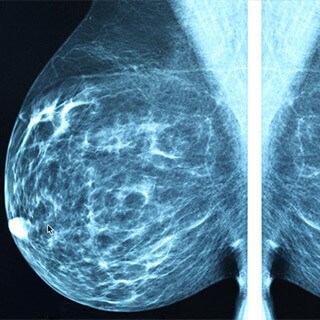

Demystifying the Mammogram Controversy

At the heart of the controversy is a question experts have been debating for years: when should routine mammograms begin for women younger than age 50? No one disputes that mammography saves lives. It is the best tool we have to find breast cancer when it is most curable, but it is also an imperfect technology. Mammograms identify breast cancer in about 15% of women in their 40s, but it fails to find many other breast cancers and identifies false positives that cause anxiety and require biopsies. It finds more tumors in women over 50, simply because risk increases with age and older women’s breast tissue is more effectively screened than the dense tissue of younger women, which tends to look like cancerous tissue on a mammogram. But it’s easy to understand why women under 40 staunchly support their routine screenings. Their tumors are often more aggressive and harder to treat, so the prognosis is generally better for a 40-something woman with an early-stage breast cancer than a tumor that is found 10 years later.